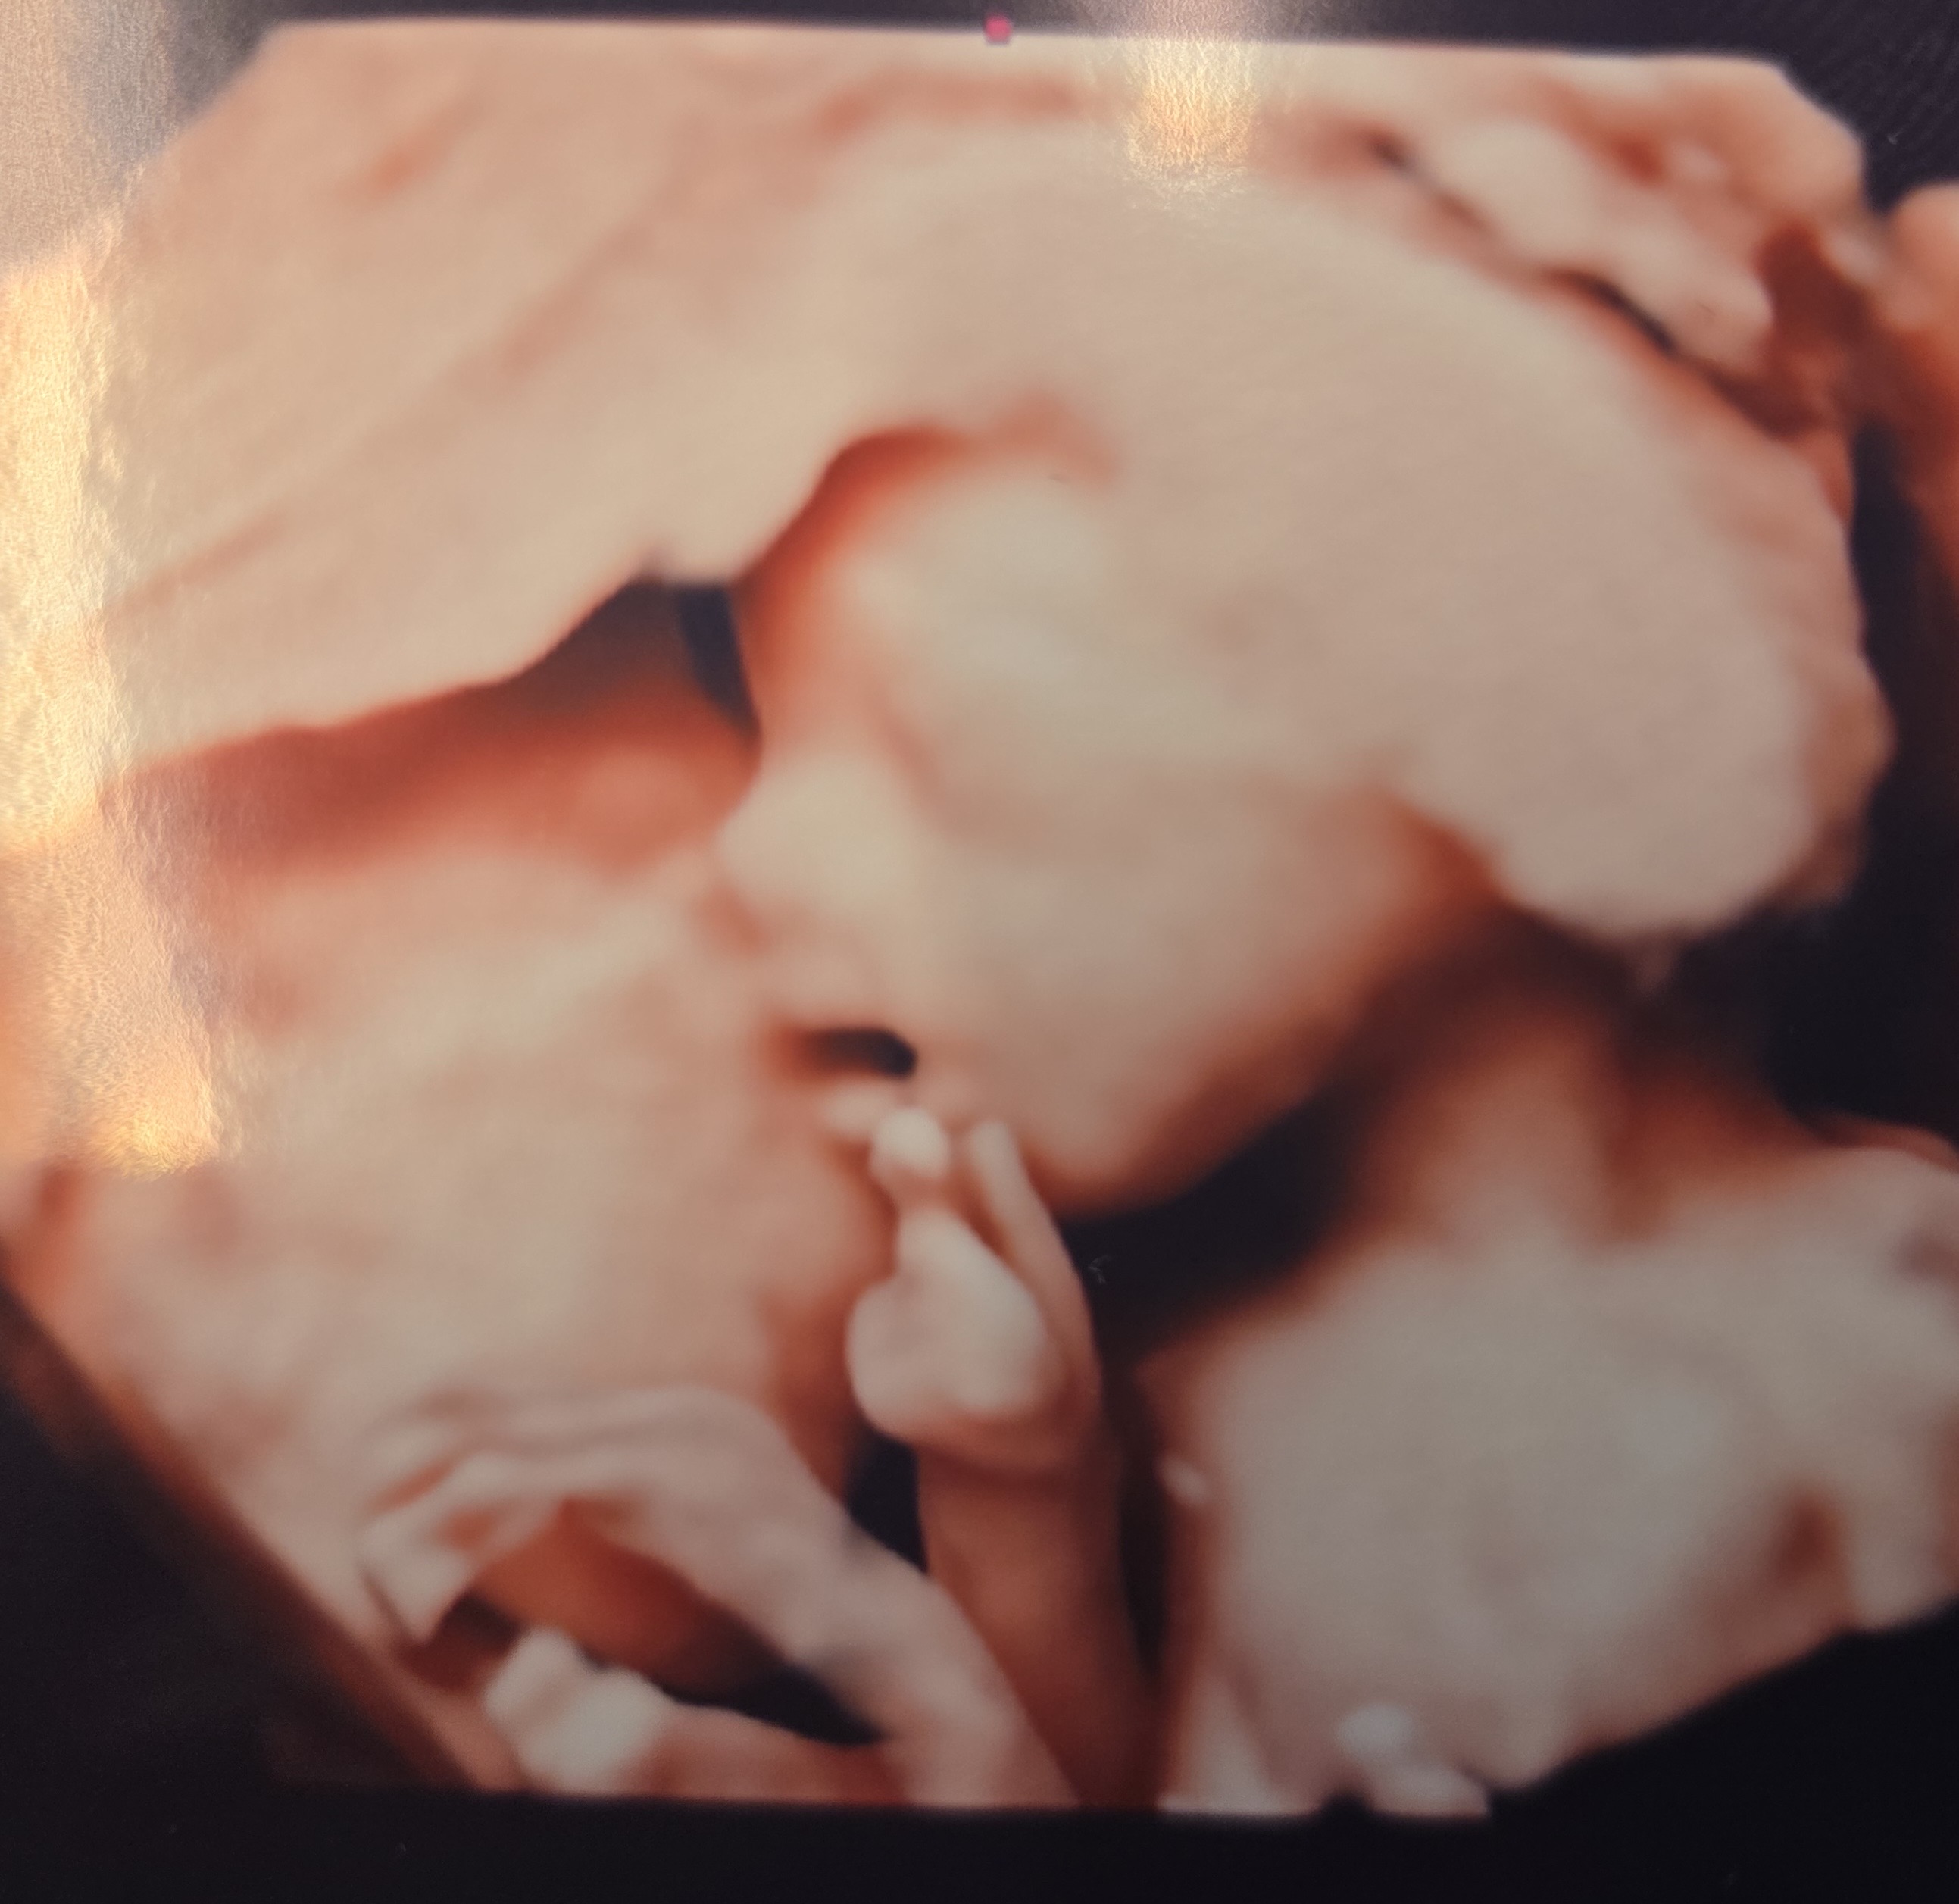

첫 입체초음파...!!

첫 입체초음파로 얼굴봤는데 이제 좀 사람같고 너무 신기해요 ㅎㅎ 다른 곳 올릴 곳이 없어서 여기라도 올려봐요..ㅎㅎㅎ